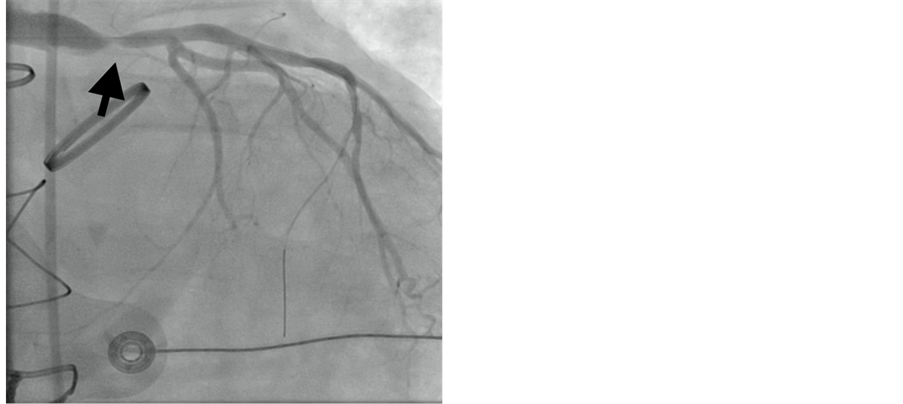

A 6 F JR4 guiding catheter 100 cm (Infiniti, Johnson and Johnson/Cordis, NJ) was used to engage the graft. A 0.014” 50 cm guide wire (Pilot, Abbott Vascular, CA) was advanced and placed distally in the native left anterior descending artery. Attempt to aspirate the thrombus with the aspiration catheter (Fetch2, Medrad Inc., PA) failed to restore any flow. Decision was made to perform mechanical thrombectomy with the 4F Angiojet catheter (Spiroflex, Medrad Inc., PA) two runs performed for 45 seconds each resulting in restoration of TIMI-3 flow (Figure 2). Repeat angiography showed that there was an anastomotic lesion of 75% in severity. A 4.0 × 15 mm bare metal stent (Vision, Abbott Vascular, CA) was deployed at 16 atms (Figure 3). A total of 1000 mcg of intracoronary adenosine was administered. ACT by HemoTech was 280 seconds and 600 mg Clopidogrel was loaded by the nasogastric tube at the end of procedure. The

Figure 2. Pre-treatment RAO angiogram showing 75% anastomotic lesion of left Cabrol graft/Left main trunk (arrow) with TIMI 3 flow.